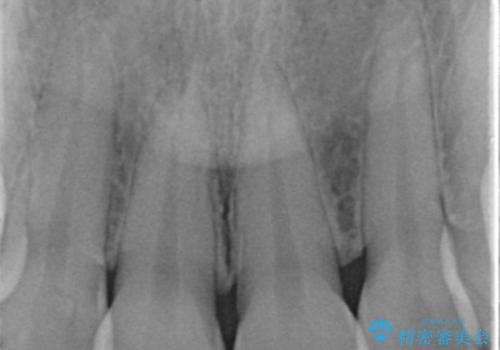

- 前歯の審美性改善と、軽度のがたつきを主訴に来院された患者様です。

マウスピース矯正を行った後、かぶせ物で審美性を改善していきます。

- インビザライン/605,000円 右上1左上1:仮歯/11,000円 ジルコニアクラウン(スタンダード)/121,000円 合計737,000円費用は治療当時の料金となります